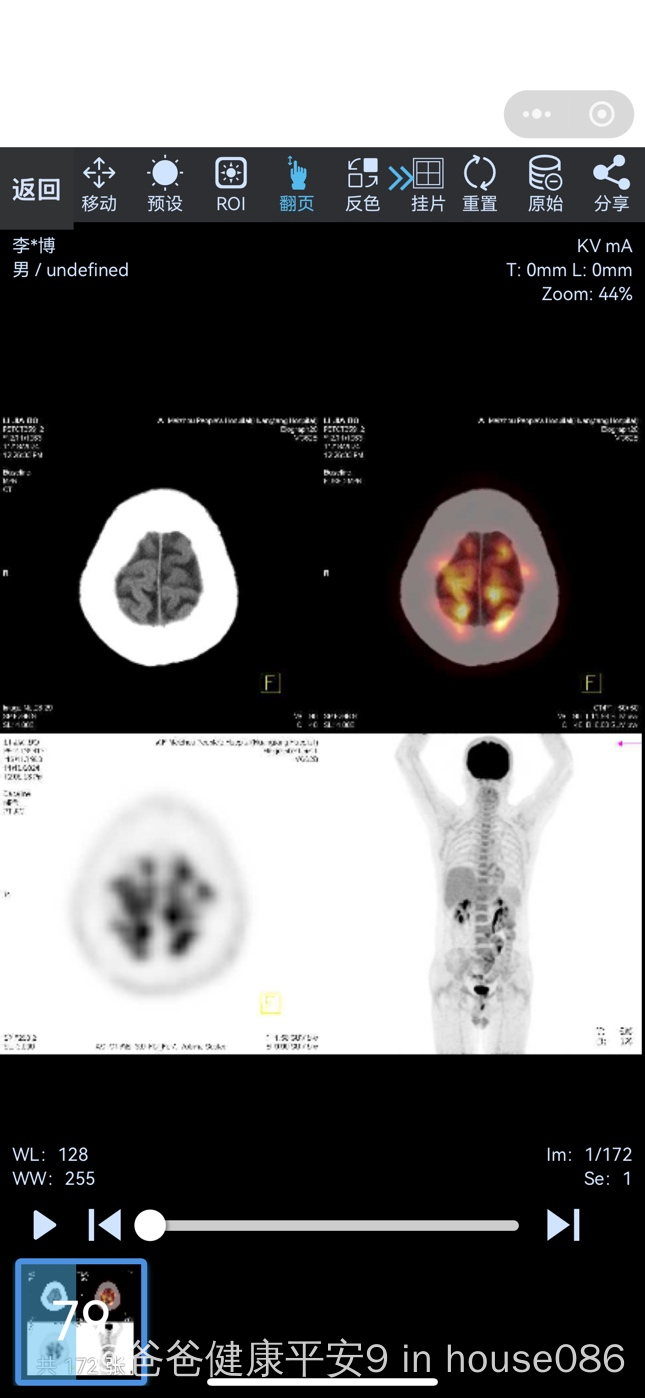

二PETCT检查的工作原理及发现癌细胞的能力 PETCT检查的工作原理相对简单在进行检查前,受检者会注射一种被提前标记过的示踪剂这种示踪剂在人体内大量聚集时,会被PETCT检查设备扫描识别到而癌细胞由于代谢活跃,非常容易代谢并聚集这种示踪剂因此,当体内有癌细胞存在时,它们会聚集到癌症部位。

临床应用PETCT检查不仅能够确诊肿瘤疾病进行肿瘤良恶性判断分期分型,还能够通过全身显像判别是否有转移灶这对于医生为肿瘤患者判断病情制定针对性强并全面有效的治疗方案具有重要意义特别是在癌症中晚期,当肿瘤出现全身转移时,PETCT检查能够帮助医生全面了解患者的病情,从而制定更加合理的治疗方案。

PETCT可以检查多种癌症,包括但不限于以下几种头部肿瘤PETCT可以检查头部是否存在恶性肿瘤胸部肿瘤如肺癌等,PETCT能够对其进行有效的筛查消化道肿瘤包括食管癌胃癌肠癌胰腺癌肝癌等,PETCT都能做出较为准确的判断生殖系统肿瘤如卵巢癌子宫癌等,PETCT也是其重要的检查手段骨。